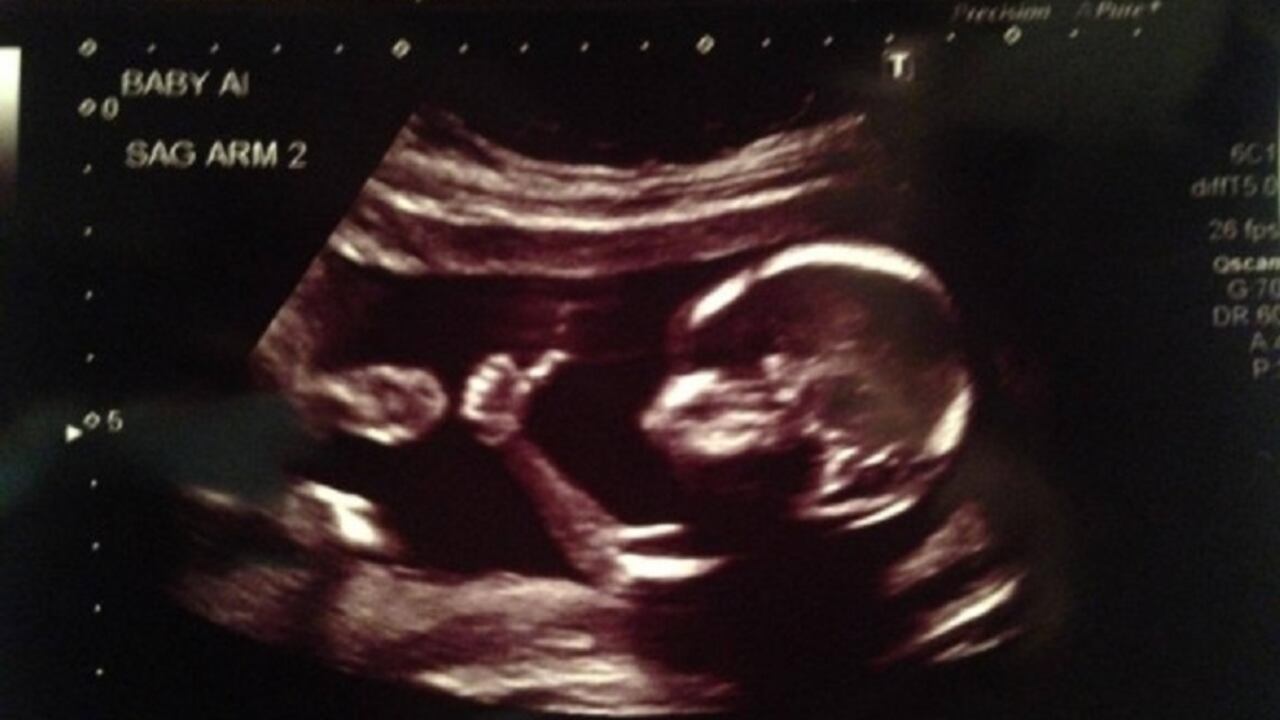

Pero sobre todo, continúa el Secretario de Salud de Cali, a los 6 meses de embarazo el feto está prácticamente formado, por lo que los médicos en estos casos apelan a la objeción de conciencia para no realizar el procedimiento. El aborto, se sabe, es un tema atravesado por asuntos ideológicos, religiosos, éticos.

“No es fácil para un especialista sacar un feto ya desarrollado, practicar el aborto, y seguir como si nada hubiera ocurrido. En parte por eso en Cali no hay entidades que lo hagan en los embarazos que superan las 24 semanas”, dice Alexander Durán.